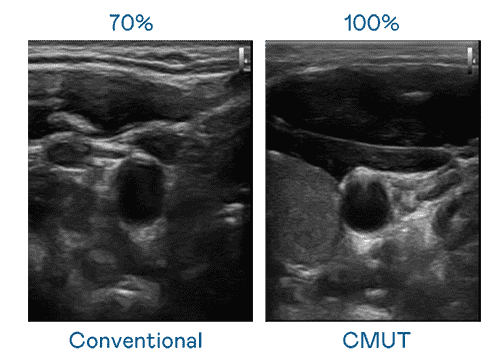

CMUT 技术是一种用电容式微机电元件来产生超音波讯号的技术。。与传统 PZT 压电式技术相比,,CMUT 频宽增加 30%,,,更宽频的超音波讯号让影像解析度大幅提升,,是实现高影像品质医疗超音波扫描、、、促进精准医疗发展的关键技术。。。

大频宽带来超清晰影像

超音波影像的解析度高低,,首先取决于探头能发出的讯号频宽。。OBPay CMUT 可提供高清晰的超音波讯号,,提供高频宽、、高灵敏度、、影像纹理细节更高的超音波影像,,,协助医护人员缩短影像判读时间及利用精准的医疗影像进行诊断。。。。